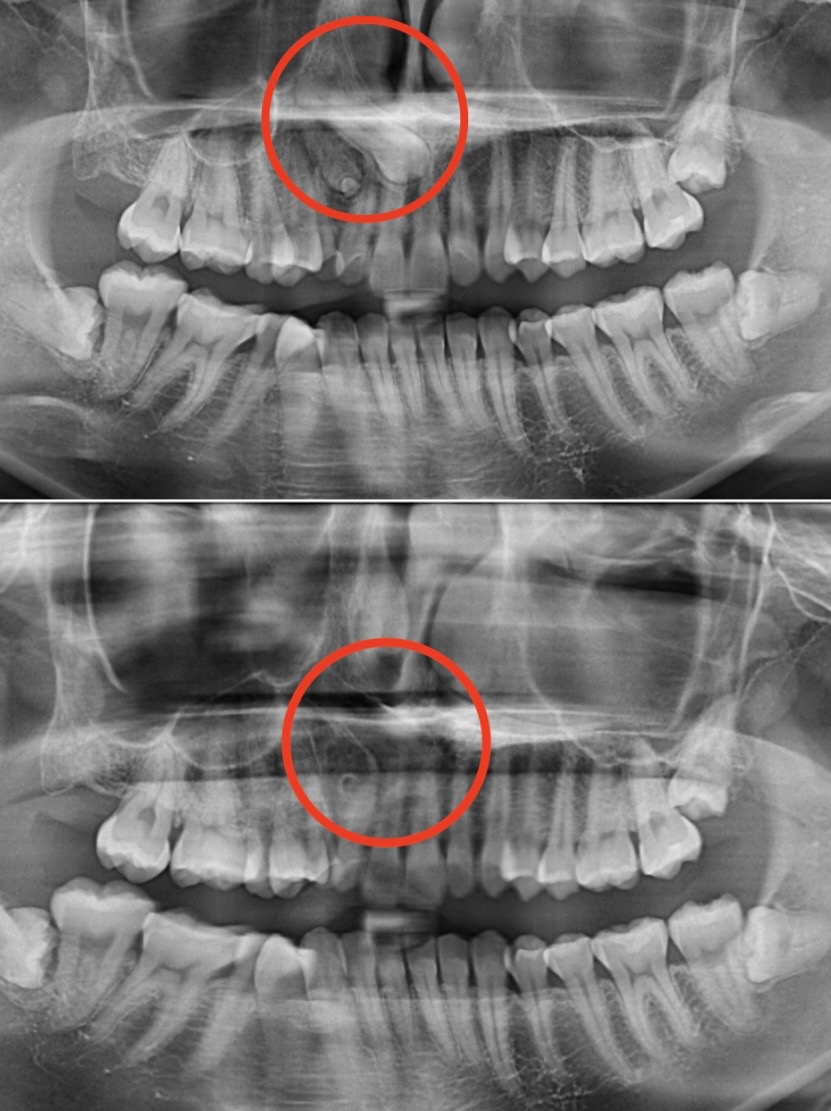

診察してみると…なんと、過剰歯が複数本あり、かなり難しい抜歯ケースでした💦

過剰歯とは、通常の本数より多く生えてしまう歯のことです。1本だけの場合もありますが、今回のように複数本ある場合は、👿歯並びが悪くなったり、👿矯正治療をスムーズに進める妨げになったりします。

さらに、奥深くに隠れている歯は、普通の抜歯よりも技術と慎重さが求められます⚡

当院ではまず、精密な診査とレントゲン検査を行い、過剰歯の位置や根の状態を確認します🔍。

今回は難しいケースでしたが、麻酔も丁寧に行い、痛みや不安を最小限に抑えながら抜歯を行いました💪✨。